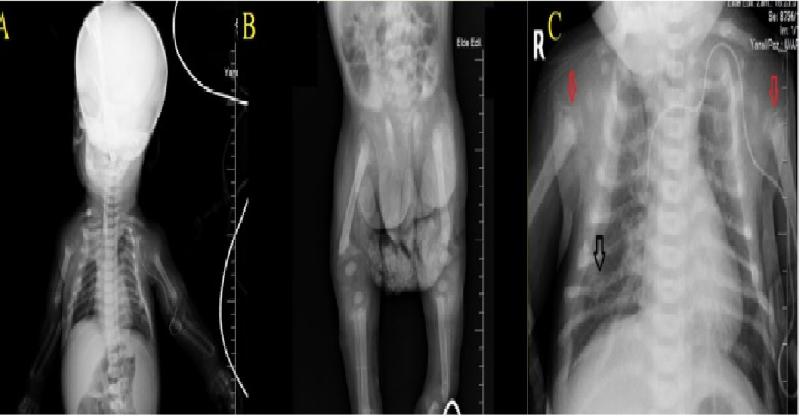

Neonatal Severe Primary Hyperparathyroidism manifested with Severe Hypercalcemia and Metabolic Bone Disease in 7 months old Infant

A 7-month-old male infant was admitted to our clinic with the diagnosis of neonatal severe primary hyperparathyroidism. It was understood from the medical history that the patient was born full-term to a 41-year-old mother via a normal vaginal route with a weight of 2.900 g and height of 51 cm, the patient had been hospitalized multiple times due t